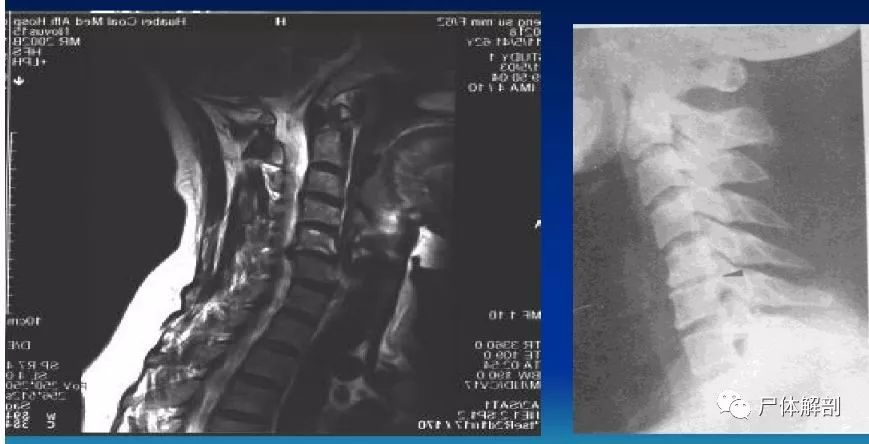

病例讨论c6c7椎体骨折伴相应水平脊髓损伤

图片尺寸1747x2000